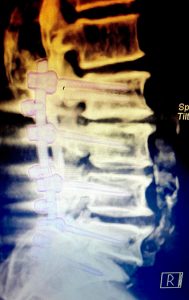

Erken teşhiste tedavinin daha başarılı sonuçlar verdiğini kaydeden Op. Dr. Serkan Zengin, “Uzun mesafe yürüme veya ayakta kalma ile bel ağrısı veya bacak ağrısı uyuşması gibi benzer belirtiler ortaya çıkabilir. Bu durumdaki hasta oturma, eğilme veya çömelme ile geçici bir rahatlama sağlayabilir. Belde kanal daralması tanısı hekimin alacağı hasta öyküsü fizik muayene ve röntgen tomografi veya mrg gibi radyolojik görüntüleme yöntemleri ile konulabilir. Tedavide ilaç ve takip yöntemleriyle hastalığın düzelme şansı oldukça yüksektir. Hastaların % 80'ine yakınında medikal ve fizik tedavi yöntemleri başarılı sonuç vermektedir. Burada erken teşhis, tedavi başarısını önemli ölçüde artırmaktadır. Erken evrede kas ağrısı, bel, boyun ve omurga hastalıklarında cerrahi müdahaleye gerek kalmadan büyük oranda tedavi edilebilmektedir. İleri düzeyde darlık ve şiddetli ağrısı olan hastalarda 3-6 aylık medikal tedaviye yanıt alınamadığı zaman cerrahi tedavi yöntemi uygulanabilir” ifadesini kullandı.

Operasyon hakkında bilgi veren Op. Dr. Serkan Zengin, “Cerrahi tedavide kişinin hastalık seviyesine göre bir operasyon planlanmaktadır. Farklı seviyelerde sıkışma ve kemik daralması varsa büyüyen kemik dokusu küçültülür, omurga kanal çapı genişletilerek sıkışan sinirlerin üzerindeki baskı azaltılır ve vidalarla omurga sabitlenir. Platin vidalar ameliyattan sonra 6 hafta süre içerisinde kemik ile kaynaşmaktadır. Böylece omurga taşıyıcı işlemine de devam edebilir. Ameliyattan sonra, genellikle hasta 2 gün içerisinde taburcu edilir. Operasyon sonrasında beli zorlayıcı hareketlerden ağır kaldırmaktan ve darbelerden hastanın kendini koruması gerekmektedir” dedi.